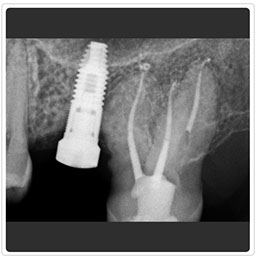

Radiografía Control de Implante